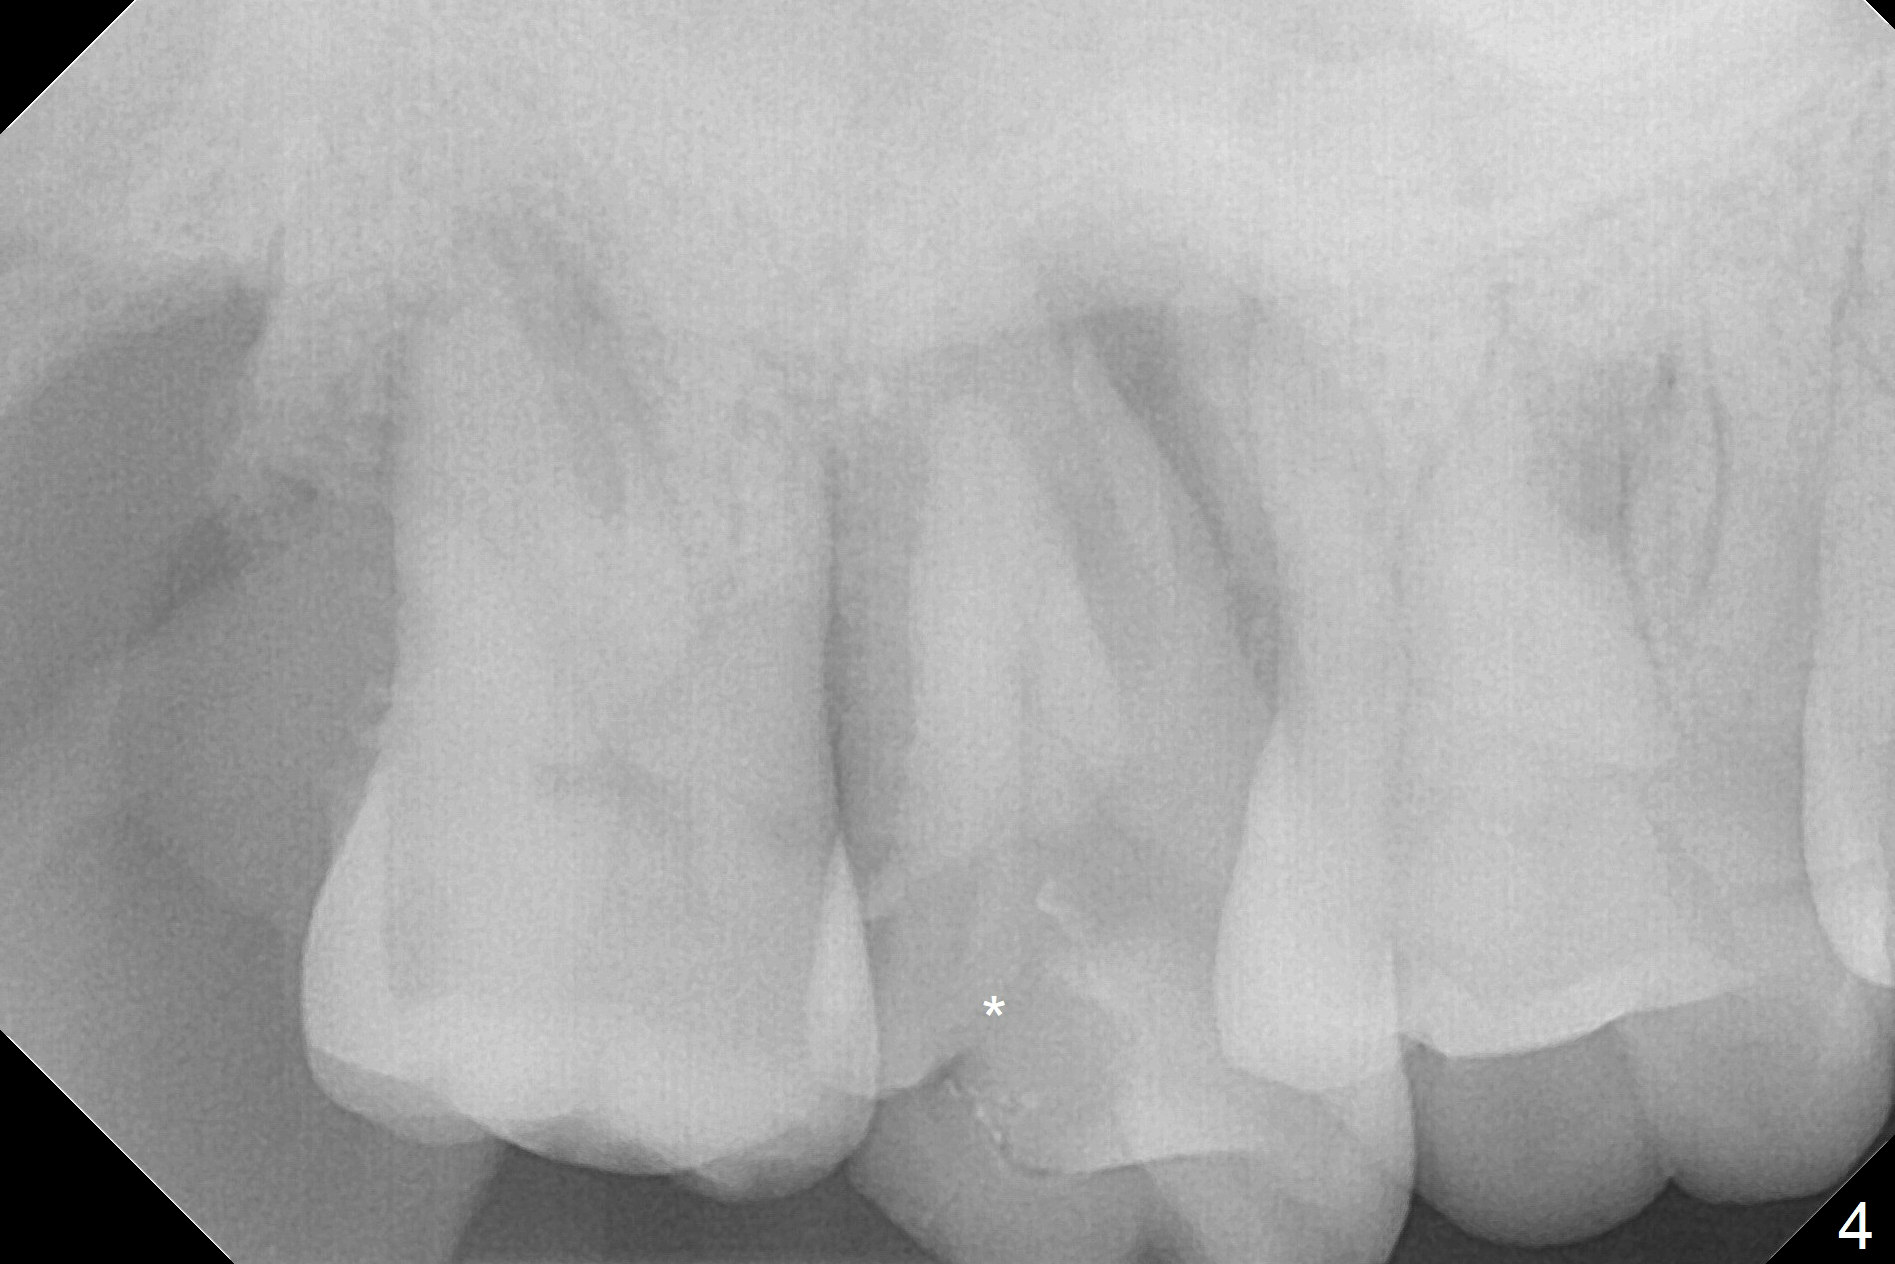

When the 59-year-old man returns for #24 implant placement, the tooth #2 is found to have crack (Fig.1,2 arrowheads), associated with buccal and palatal fistulae (*) and loss of amalgam (Fig.4 *). Abundant granulation tissue is attached to the roots of the affected tooth (Fig.3), indicating severe bone loss. There is a plateau associated with the septum and buccal sockets, which is the site of osteotomy. Magic split and 3 and 3.8 mm Magic Expanders are used to initiate osteotomy. After use of 4.3 mm Magic Drill for about 3 mm, Osteogen plug and allograft are used for sinus lift, followed by insertion of a 4.5x11 mm dummy implant (Fig.5). When a 5.5x9 mm dummy implant is placed with stability, it appears to be seated cervical (Fig.6,7). When a 6x9 mm IBS implant (definitive) is placed with a 6.5x5.5(4) mm abutment, they are seated too deep for provisional (Fig.8). The implant/abutment are removed and replaced by a 6.5x11 mm one in a shallower position; after trimming the same abutment as mentioned above (Fig.9), an immediate provisional is fabricated to keep bone graft in place. Fabrication of Tap with soft tissue markers will reduce the chance of miscalculation and waste of implants. The coronal threads of the implant are covered with bone 6 months postop (Fig.10). One month later when a permanent crown tries in, the implant is found to be loose and tender. A healing abutment is placed. Six months later, the patient returns for crown retry-in. The tooth #1 seems to have shifted mesially (Fig.11 arrow). When the abutment is placed, the implant remains tender and loose. After implant removal with a wrench, there is no granulation tissue or bony defect, including the intact sinus floor (Fig.12 <). Since the tooth #1 has deep periodontal pockets and mobility, the tooth is extracted with abundant granulation tissue. After debridement, Osteogen plug is placed in the socket of #1, while Vanilla graft is placed at the site of #2 (Fig.13 *). Three weeks later, the socket of #2 heals with exposure of Osteogen plug (Fig.14 (B: buccal)).